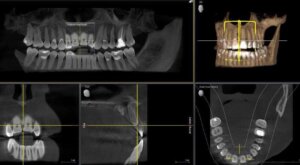

Diese Technik benötigt nur einen Bruchteil der konventionellen Strahlendosis und kommt ohne Filme, Entwicklermaschinen und giftige Chemikalien aus. Die Röntgenbelastung wird um circa 90% zur konventionellen Röntgentechnik reduziert.